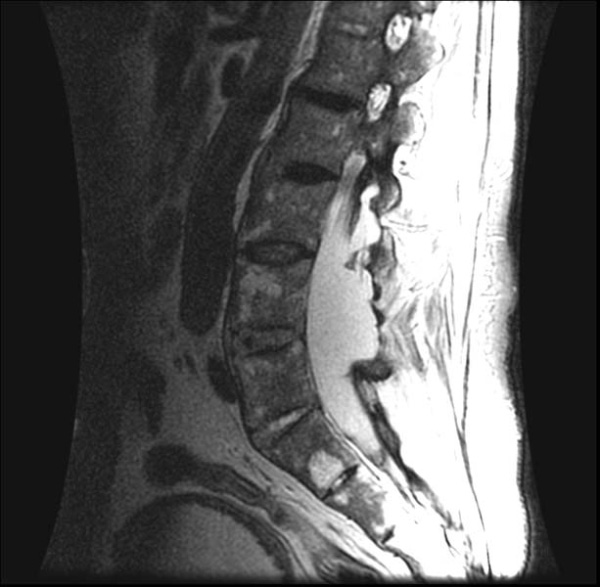

Sau đây là một số hình ảnh viêm cột sống dính khớp trên X-quang: